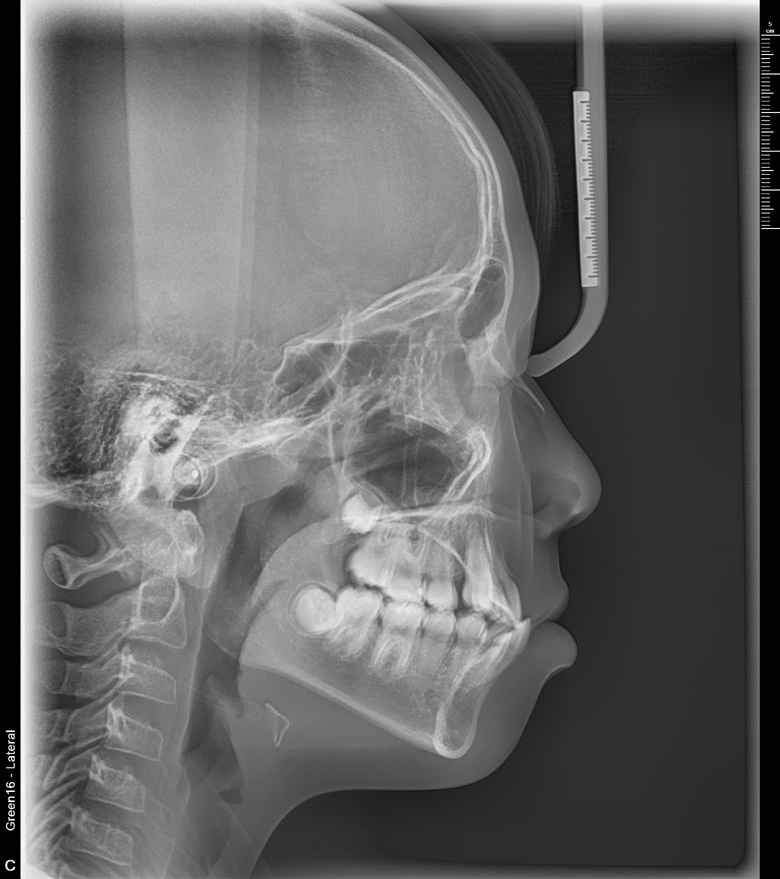

치료 후 사진입니다.